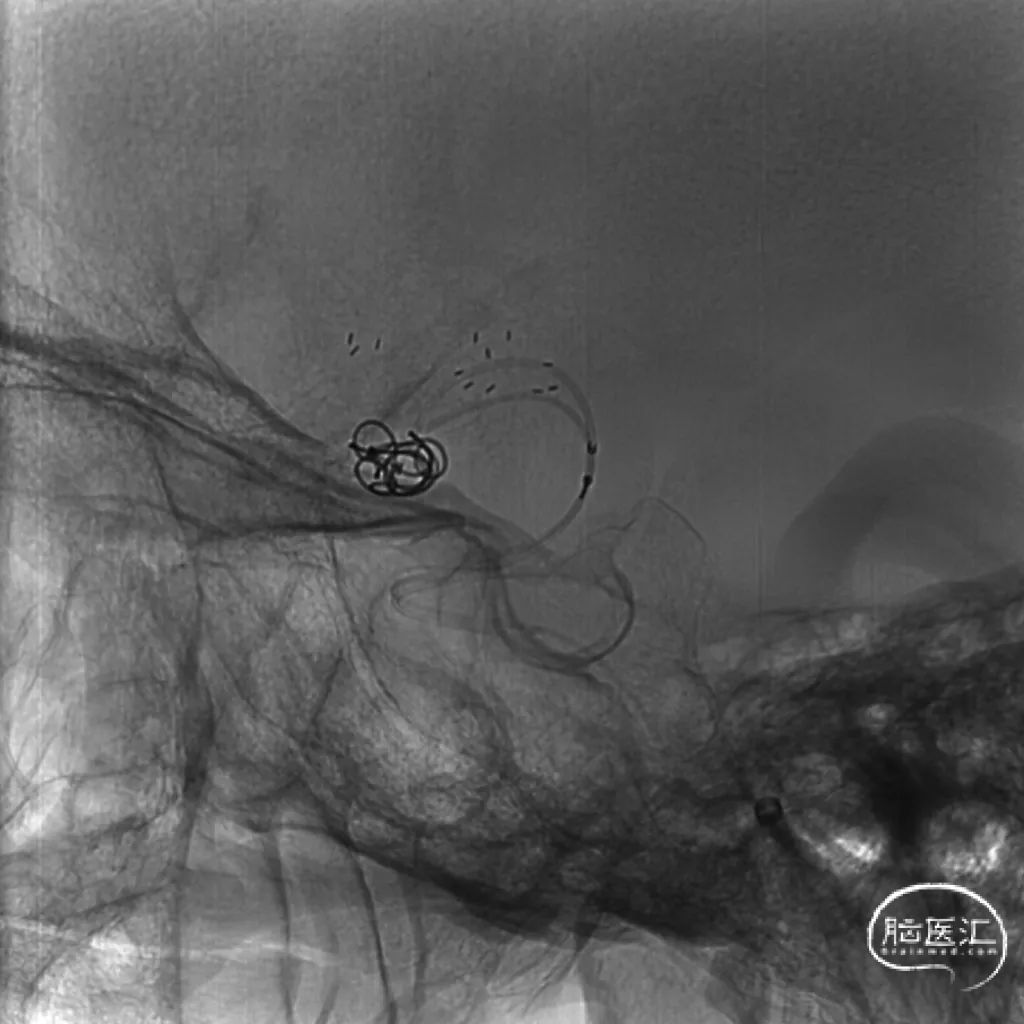

术后影像

术后即刻工作位造影及蒙片:

术后即刻正位造影及蒙片:造影显示瘤体致密栓塞,支架贴壁和导流良好。